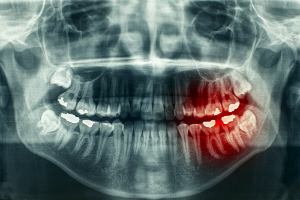

The purpose of X-Rays is to pinpoint problems and avoid further complications. Without them, we couldn’t find decay under fillings or between teeth, we couldn’t find abscesses or tumors in gums and bone, and we couldn’t detect faulty development of adult or wisdom teeth. We also wouldn’t be able to see the formation of pockets around teeth or the loss of bone caused by gum disease.

Furthermore, the risks are widely misunderstood, and dental X-Rays, in particular, use less radiation than just about any other variety. During a checkup that includes either 4 bitewing or 1 panoramic X-Ray, patients receive a dose of .005 or .01 millisieverts (mSv) respectively. That’s the equivalent of about 1 or 2 days of natural background radiation. Compare that with full-chest X-Rays that result in 10 to 20 times as much exposure (0.1 mSv), or pelvic X-Rays that require 60 to 120 times as much (0.6 mSv).